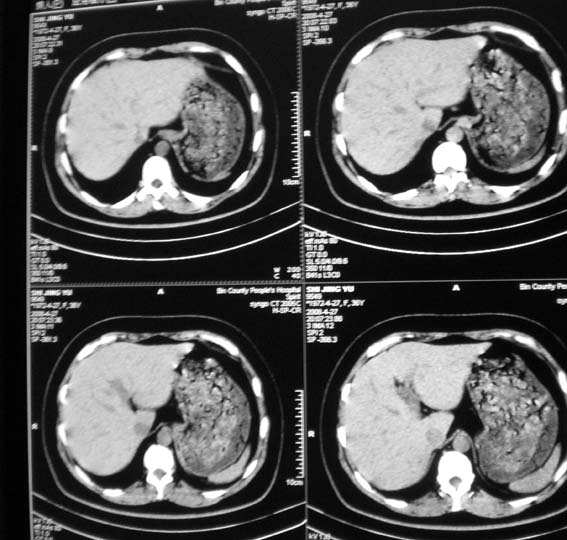

标题: CT13126:腰痛,肾区痛。 [打印本页]

标题: CT13126:腰痛,肾区痛。

女,36岁,腰痛,肾区痛曾有肾囊肿史。

腹部未见明显异常

未见异常.